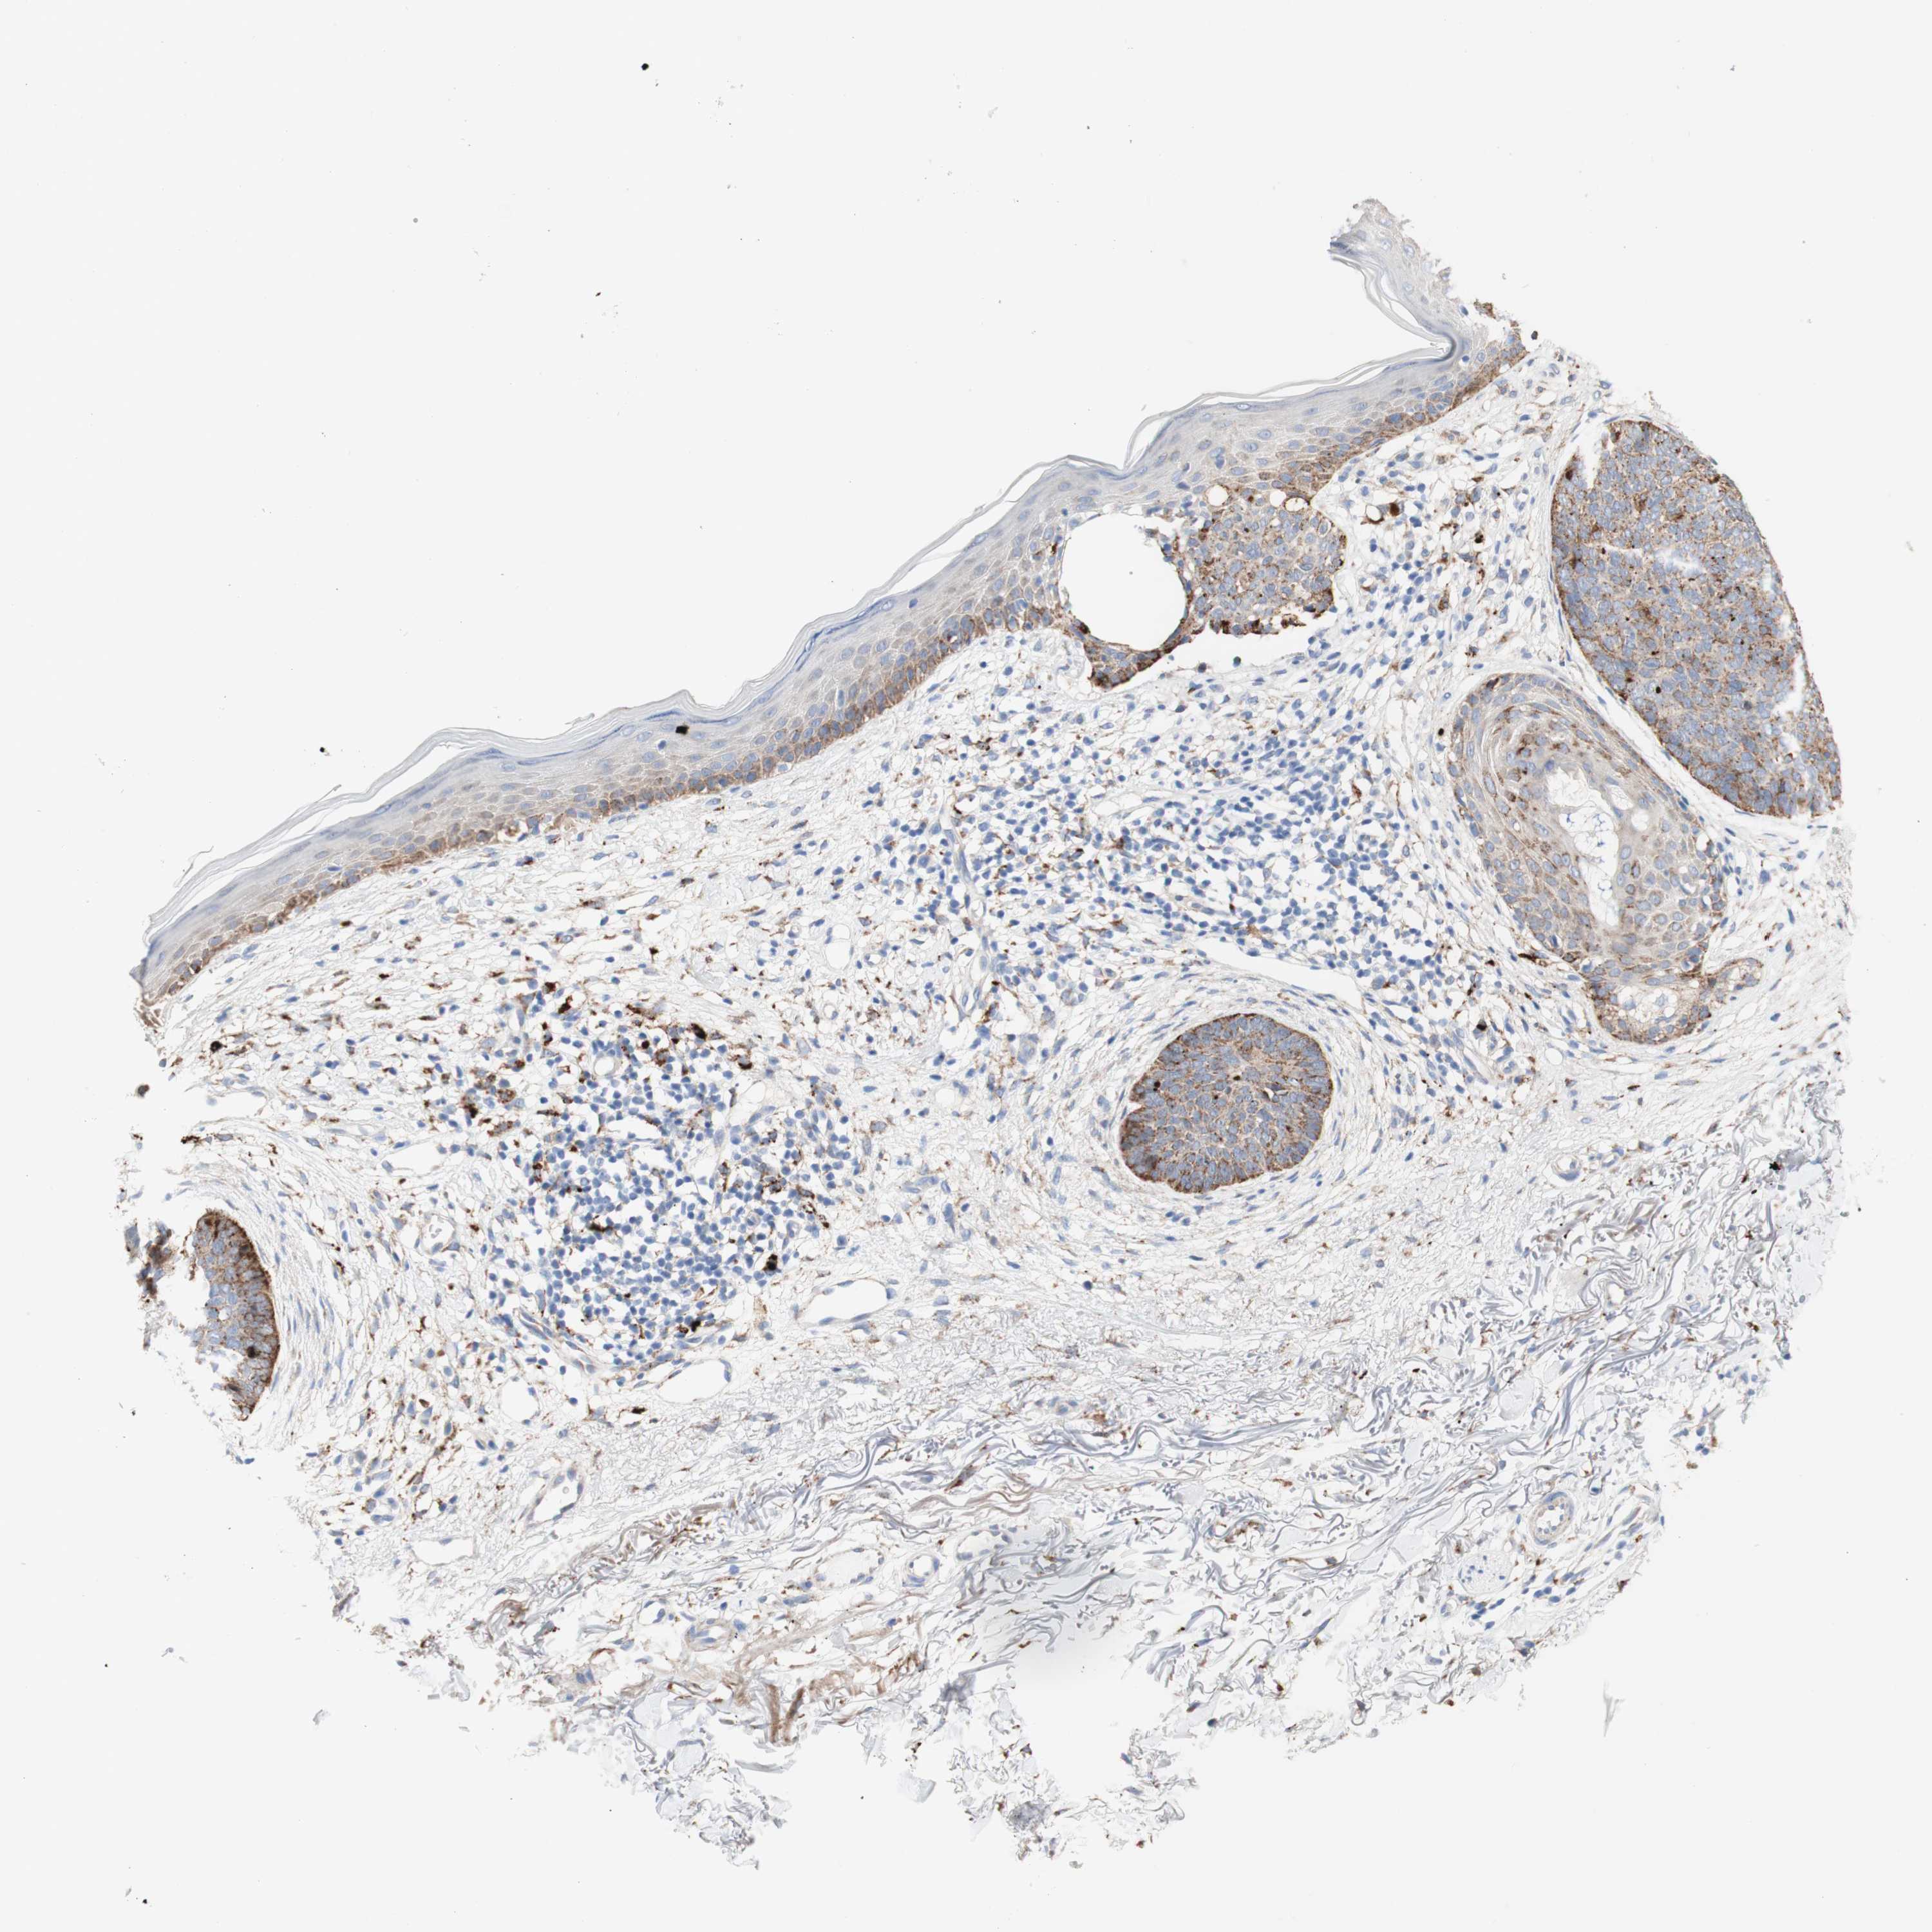

SKIN CANCER - Protein expressioni

A mouse-over function shows sample information and annotation data. Click on an image to view it in a full screen mode. Samples can be filtered based on level of antibody staining by selecting one or several of the following categories: high, medium, low and not detected. The assay and annotation is described here.

Antibody staining in the annotated cell types in the current human tissue is reported as not detected, low, medium, or high, based on conventional immunohistochemistry profiling in selected tissues. This score is based on the combination of the staining intensity and fraction of stained cells.

Each image is clickable and will lead to virtual microscopy that enables deeper exploration of all samples and also displays staining intensity scores, fraction scores and subcellular localization as well as patient and tissue information for each sample.

Antibody HPA008902

Squamous cell carcinoma, NOS

Basal cell carcinoma